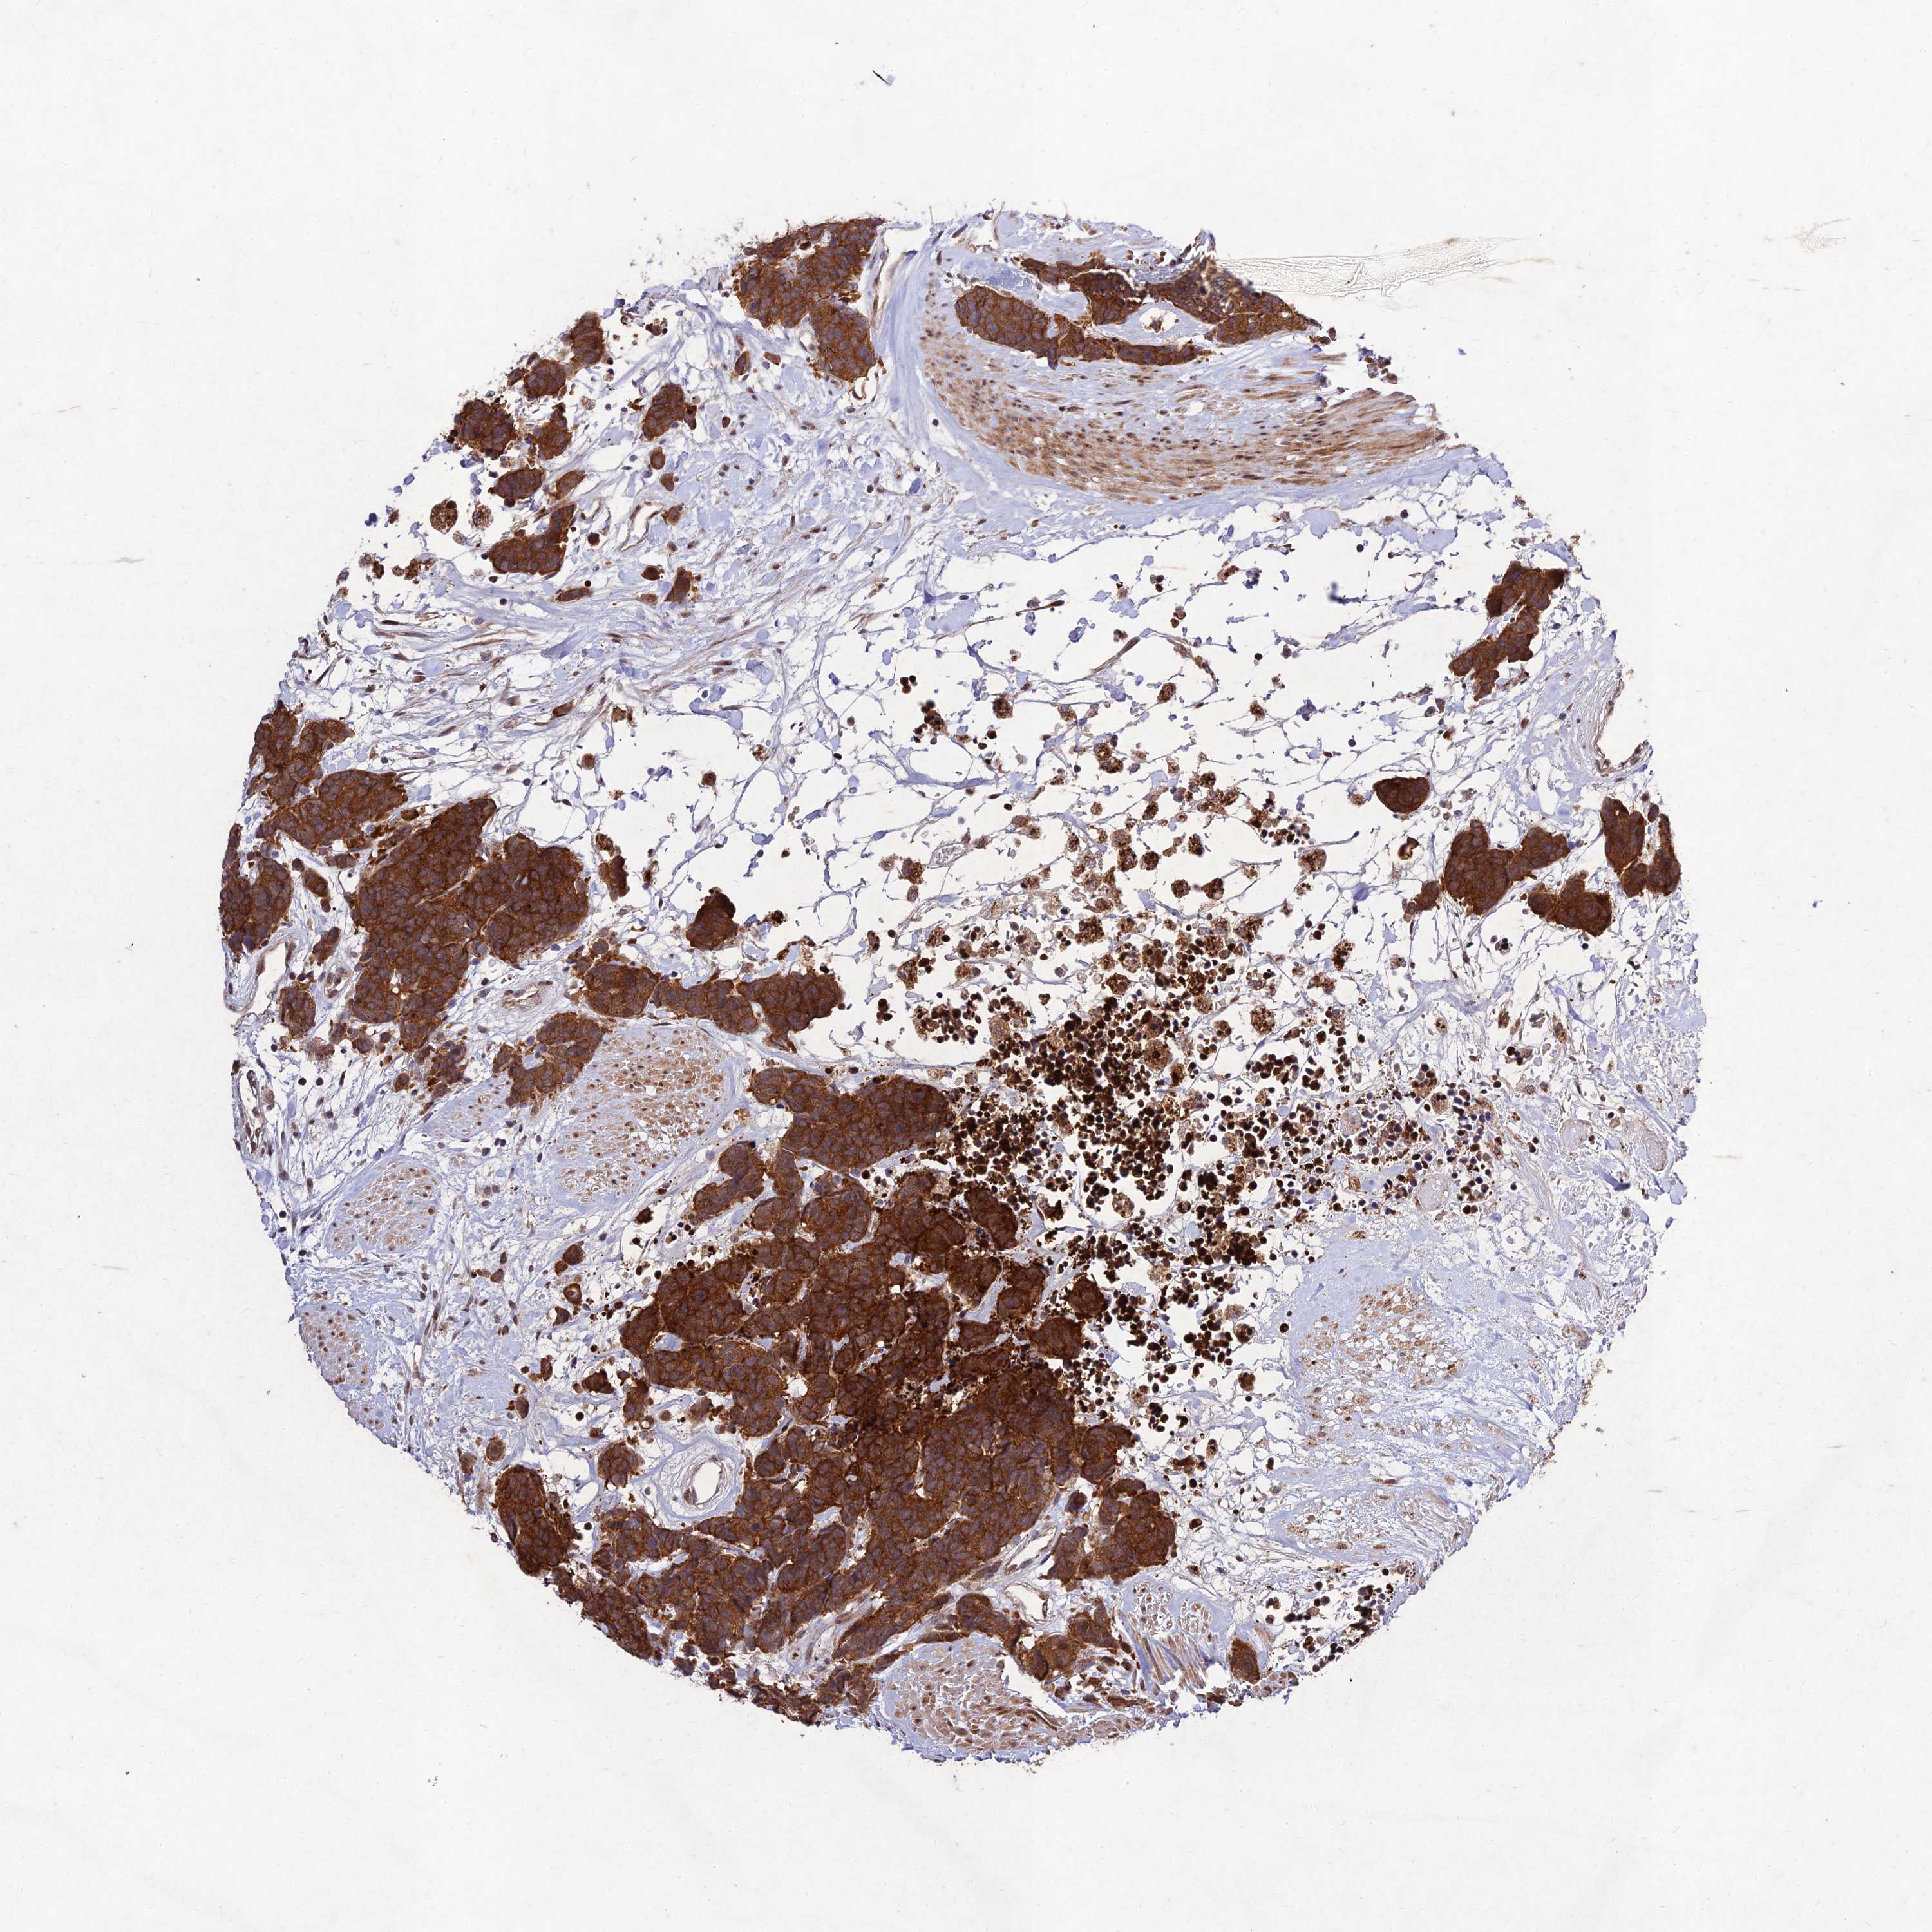

CARCINOID - Protein expressioni

A mouse-over function shows sample information and annotation data. Click on an image to view it in a full screen mode. Samples can be filtered based on level of antibody staining by selecting one or several of the following categories: high, medium, low and not detected. The assay and annotation is described here.

Antibody stainingi

Antibody staining in the annotated cell types in the current human tissue is reported as not detected, low, medium, or high, based on conventional immunohistochemistry profiling in selected tissues. This score is based on the combination of the staining intensity and fraction of stained cells.

Each image is clickable and will lead to virtual microscopy that enables deeper exploration of all samples and also displays staining intensity scores, fraction scores and subcellular localization as well as patient and tissue information for each sample.

Antibody HPA041071

Antibody HPA044233

Staining

High

Medium

Low

Not detected

Intensity

Strong

Moderate

Weak

Negative

Quantity

>75%

75%-25%

<25%

None

Location

Nuclear

Cytoplasmic/membranous

Cytoplasmic/membranous,nuclear

Carcinoid, malignant, NOS

Carcinoma, NOS